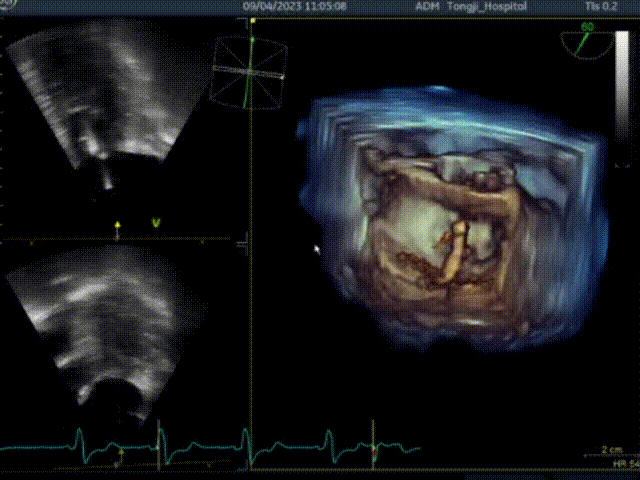

一、经心尖不停跳室间隔切除术

患者术前大量反流,前叶SAM征,室间隔增厚最厚处13mm

二、行经心尖介入二尖瓣夹合手术ValveClamp

ValveClamp抓捕瓣叶并收入闭合环内

该患者为老年女性,左室流出道压差134mmHg,二尖瓣前后叶冗长,即便切除了增厚的心肌组织,二尖瓣仍然可能存在反流,同时前叶冗长有阻挡流出道的风险,术前魏翔教授团队就治疗方案进行了充分的商议,最终提出使用两种来自中国原创的新器械(心肌旋切系统+ValveClamp),在同一切口下行不停跳魏氏心肌旋切术加经心尖介入二尖瓣夹合术。